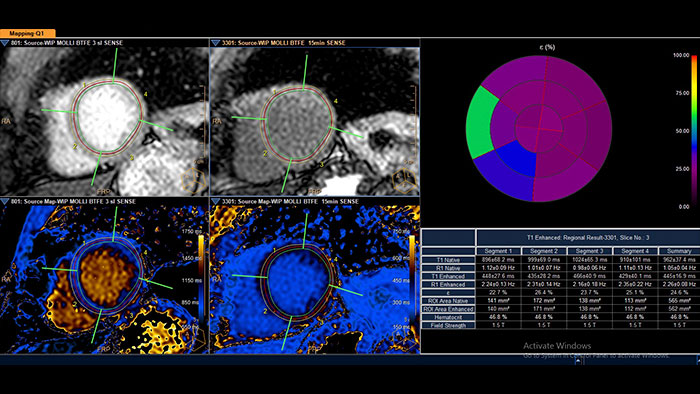

- Cardiac Quantitative Mapping

-

MR Cardiac Quantitative Mapping

Assess myocardial tissue characteristics

The MR Cardiac Quantitative Mapping helps you assess and review myocardial tissue characteristics in multiple, user-defined, field-strength specific lookup tables.

Benefits

- Review global and diffuse myocardial pathologies by means of T1 maps, T2 maps, and T2* maps.

- Manual and automatic motion correction tools are provided which may enhance map calculations.

- Expended acquisitions support: Molli, shMolli, SASHA, T2prep.